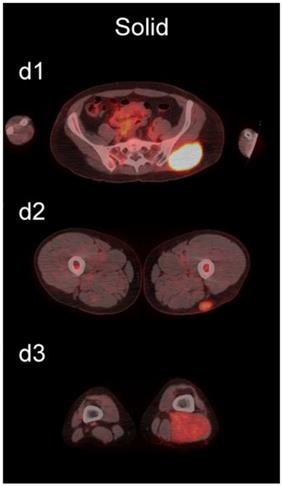

The readers scored the SP of the STSs and BFs on the 4-point avidity scale (Fig. 1). Reader agreement was substantial (κ = 0. 61) and varied among the different SPs, being highest for the thin SP (κ = 0.70) and lowest for the thick SP (κ = 0.46, Table 4). Examples of SPs with 100% reader agreement are shown in Fig. 3.

Figure 3

Examples of lesions with 100% observer agreement on assessment of SP. a Thin SP a1 A 77-year-old woman with a seroma (arrow) 17 days following excisional nodal biopsy (SUVmax = 1.7). a2 A 66-year-old woman with a seroma (arrow) 3 months following excisional nodal biopsy (SUVmax = 2.0). a3 A 21-year-old man with a seroma (arrow) 10 days following excisional nodal biopsy and hydrocele repair (SUVmax = 3.9). b Moderate SP: b1 A 46-year-old man with undifferentiated sarcoma (SUVmax = 19.4). b2 A 38-year-old man with a fungal abscess (SUVmax = 11.6). b3 A 78-year-old woman with recurrent myxoid pleomorphic undifferentiated sarcoma (SUVmax = 5.9). c Thick SP: c1 A 67-year-old man with metastatic undifferentiated sarcoma (SUVmax = 6.3). c2 A 65-year-old man with pleomorphic undifferentiated sarcoma (SUVmax = 30.3). c3 A 45-year-old man with synovial sarcoma (SUVmax = 10.9). d Solid SP: d1 A54-year-old woman with rhabdomyosarcoma (SUVmax = 15.7). d2 A 43-year-old man with pleomorphic undifferentiated sarcoma (SUVmax = 2.7). d3 A 48-year-old woman with myxoid liposarcoma (SUVmax = 2.9).

The SP of STSs was more likely to be assessed as thick or solid by all readers (p<0.0001). Modeling the diagnostic efficacy of a system that classified lesions with a thick or solid SP as an STS yielded an inter-reader averaged sensitivity and specificity of 69% and 98%, respectively.

We also examined the contribution SP to the differentiation of STSs from BFs. SP has not been as extensively investigated as SUV [36-42], and may provide additional information about the biological behavior of soft-tissue lesions on 18F-FDG PET [37]. SP can be assessed qualitatively or quantitatively. Qualitative assessments of heterogeneity, degree of peripheral nodularity, and apparent peripheral thickness of lesions have been used in the past to differentiate benign from malignant lung [38] and peripheral nerve sheath [39] tumors, and to distinguish between high-grade and low-grade STSs [36]. Quantitative algorithms for objective characterization of SP have been used to estimate prognosis in patients with STSs [37, 40, 41] and to assess treatment response in patients with head and neck cancers [42]. Widespread adoption of these quantitative methods has likely been hampered by practical concerns such as time constraints in busy clinical practices. We chose to focus on a qualitative assessment of SP to provide a more readily applied clinical method using an intuitive 4-point scale (Fig. 1) for subjective evaluation of SP (Fig. 3).